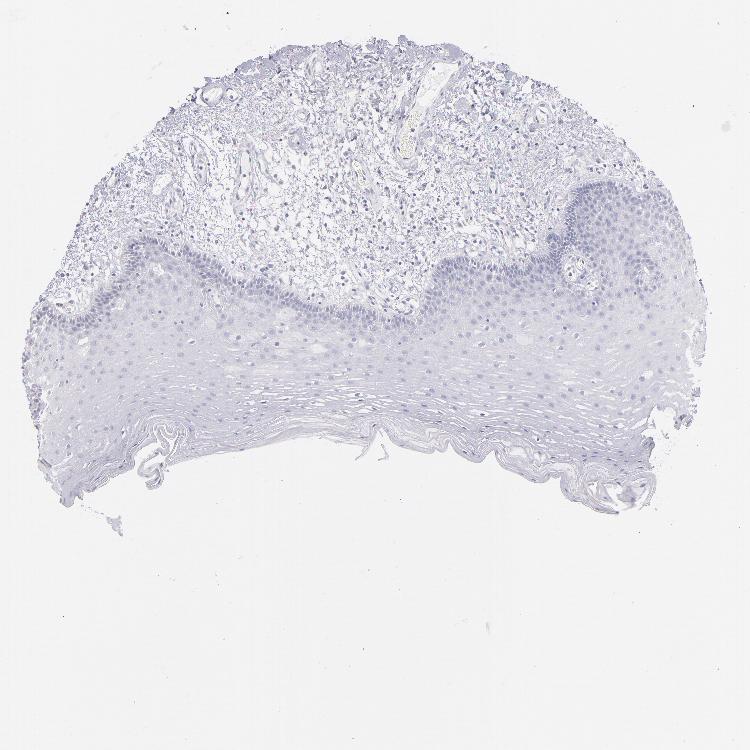

TISSUE PRIMARY DATA ORAL MUCOSA Show tissue menu

Oral mucosa

ORAL MUCOSA - Antibody stainingi

Antibody staining in the annotated cell types in the current human tissue is reported as not detected, low, medium, or high, based on conventional immunohistochemistry profiling in selected tissues. This score is based on the combination of the staining intensity and fraction of stained cells.

Each image is clickable and will lead to virtual microscopy that enables deeper exploration of all samples and also displays staining intensity scores, fraction scores and subcellular localization as well as patient and tissue information for each sample.

Antibody HPA001928

Squamous epithelial cells Not detected